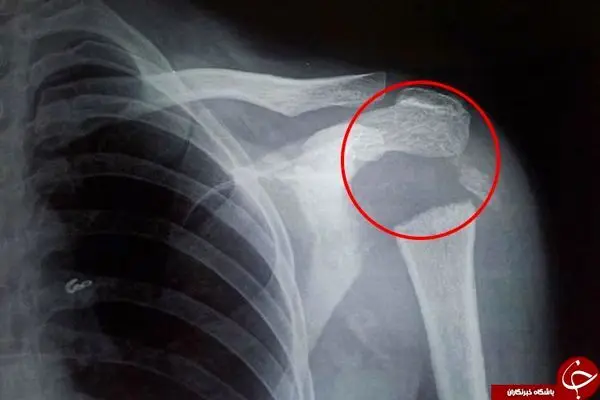

یک زن جوان هندوستانی در اثر ناپدید شدن قسمتی از استخوان شانه اش قادر است دست راست خود را به حالت 180 درجه بچرخاند. این زن 37 ساله که مدت 3 ماه است دچار درد در ناحیه شانه راست خود شده مجبور است تا از دست چپ خود برای انجام اموراتش استفاده کند. پس از انجام آزمایش پزشکان متوجه شانه بسیار انعطاف پذیری این زن شدند که او را قادر می ساخت تا دست خود را به حالت 180 درجه بچرخاند. این آزمایش اسکن نشان داد بخش حلقوی دست این زن که با بازوهای او متصل می شود ناپدید شده است.